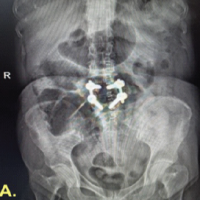

Postoperatively, passive range-of-motion exercises were initiated at 2 weeks, followed by active exercises beginning at three weeks. At 6 weeks, the patient developed recurrent shoulder pain and mechanical catching. Despite continued rehabilitation, symptoms gradually worsened. At 6 months postoperatively, MRI demonstrated a hypointense structure within the subacromial bursa (Fig. 3). Suspecting this to be the cause of symptoms, repeat arthroscopy was performed.

Figure 3: Post-operative coronal T2-weighted Magnetic resonance imaging (MRI) showing loose body within subacromial bursa. Coronal T2-weighted MRI of the right shoulder performed 6 months postoperatively, demonstrating a hypointense structure (arrowhead) within the subacromial bursa, consistent with a loose body formation. The previously torn rotator cuff appears to have been repaired.